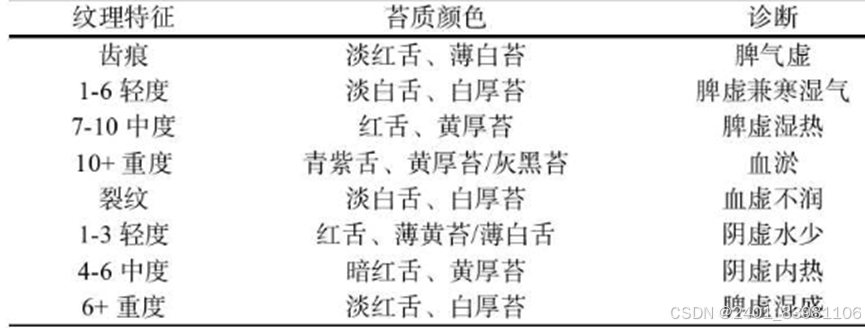

舌象分类

二:苔质识别分类